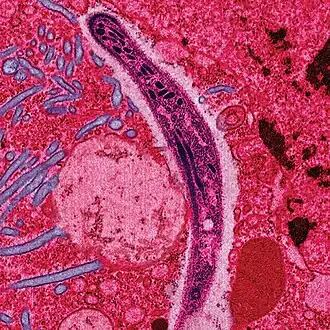

| O parasita Plasmodium ao atravessar o citoplasma de uma célula epitelial da fêmea do mosquito, na forma com que penetra no corpo do ser humano e de outros vertebrados. | |